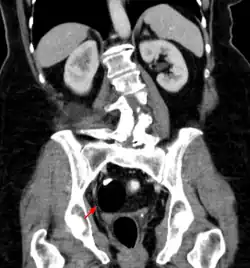

Les tératomes de l'ovaire

Les tératomes immatures de l’ovaire, souvent détectés à l'échographie, TDM ou IRM[21] sont potentiellement malins tout comme les tératomes testiculaires, qui sont généralement moins bien différenciés (donc avec un pronostic plus sombre). Des effets hormonaux, systémiques ou éloignés (ex. : encéphalite limbique paranéoplasique, encéphalite paranéoplasique anti-NMDAr)[22] sont possibles. Les métastases sont rares mais possibles (ex. : métastases neuroïdes matures d’un tératome ovarien[23]). Après ablation, des récidives sont possibles[24].